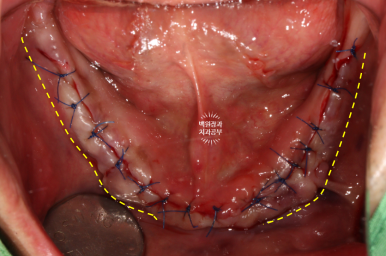

열심히 예쁘게 꿰매드리고 나서 .. (생각보다 너무 깔끔하잖아..?)

보면 뼈이식이 많이 된 것 같지 않나요?

상당히 볼쪽으로 뚱뚱해진 잇몸뼈를 보실 수 있을겁니다.

유독 앞니의 뼈가 얇아 더 많이 뼈이식을 했던 기억이 납니다.